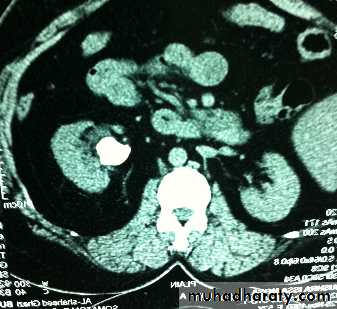

Ct enhanced

Big simple renal cyst(non enhancing mass homogenous) treatment is conservative or drainge if symptomaticWhat's the Diagnosis?